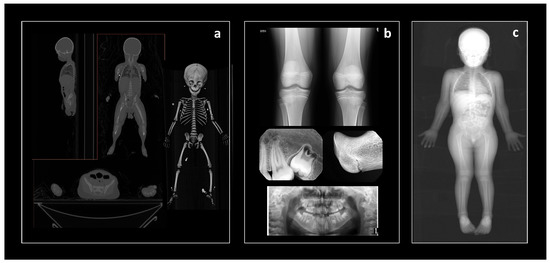

The data were collected from four types of anonymized medical images: CT scans, Lodox Statscans, conventional radiographs, or panoramic radiographs (Figure 2). The CT scan and Lodox Statscan images follow the Digital Imaging and Communications in Medicine (DICOM) Standard for facilitated storage (.dcm format), transfer, and visualization of the images without any loss of information and data [36]. DICOM images require medical imaging visualization software for data collection. The two-dimensional conventional (Angola, Colombia) and panoramic (Brazil) radiographs are stored in other formats common to digital images (e.g., .JPG, .TIFF formats). Other medical imaging databases composed of .JPG files have been set up and studies have shown that loss of information is minimal and image resolution is preserved after conversions from .dcm files [34,37]. However, because of the possibility of distortion and/or magnification associated with these three radiographic samples, only ordinal data (i.e., developmental stages), not continuous data (i.e., measurements), were collected on them. The collaborators from hospitals and/or dental practices usually contributed element- or region-specific images of living individuals. This was true for the Brazilian radiographic sample, the Dutch CT scan sample, the French CT scan sample, the Taiwanese CT scan sample, and the Angolan radiograph sample. The South African sample stemmed from a hospital (living individuals) and a medical examiner’s office (deceased individuals) that used Lodox Statscan to produce full-body images [31]. The Lodox Statscan is an imaging device that can generate high quality radiographic images of up to 1.8 m in length at high speed, with minimal radiation or distortion, and is routinely used in trauma and forensic cases [38]. The U.S. sample is comprised of deceased individuals and therefore the full body CT scans were generated at medical examiners’ offices in Baltimore, Maryland and Albuquerque, New Mexico. The CT scans of the individuals from Albuquerque, New Mexico are part of the NMDID virtual repository and accessible via the NMDID website (https://nmdid.unm.edu/ accessed on 1 November 2021). The only SVAD sample that had data collected from skeletal remains was Colombia. Individuals in this sample died between the 1990s and early 2000s and were exhumed from public cemeteries in Medellin and housed at the Universidad de Antioquia [39].

Figure 2.

Types of medical images used for data collection in the SVAD. (a) full-body CT scan (sagittal, frontal, transverse views) and volume rendering of the skeleton; (b) conventional radiographs, examples herein of the knees (top), teeth and proximal radius (middle), and teeth (bottom); and (c) full-body Lodox Statscan.